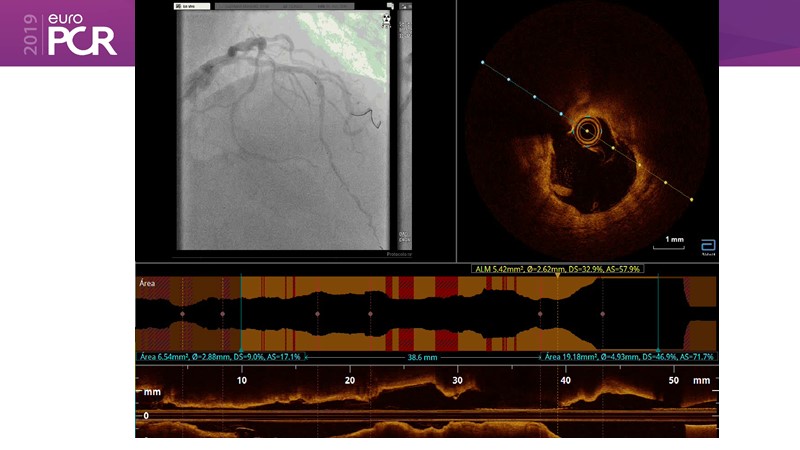

Consult this session on lithotripsy to learn about the clinical utility of IVL and the best practices when using this procedure, while discovering the best intravascular lithotripsy cases from the past year: complex PCI of severely calcified left coronary artery, heavy calcified lesions, and more!